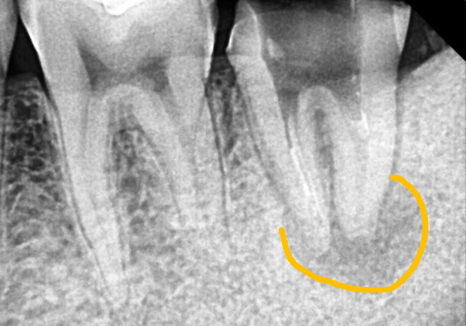

한 달 뒤,

시꺼멓게 보이던 뿌리 끝 염증이

눈에 띄게 사라진 모습!!

260219 / 260324

이제 이 치아가 잘 아물어서 환자분이

다시 편안하게 식사하실 수 있도록

정성껏 마무리해 드릴 일만 남았네요. ^^